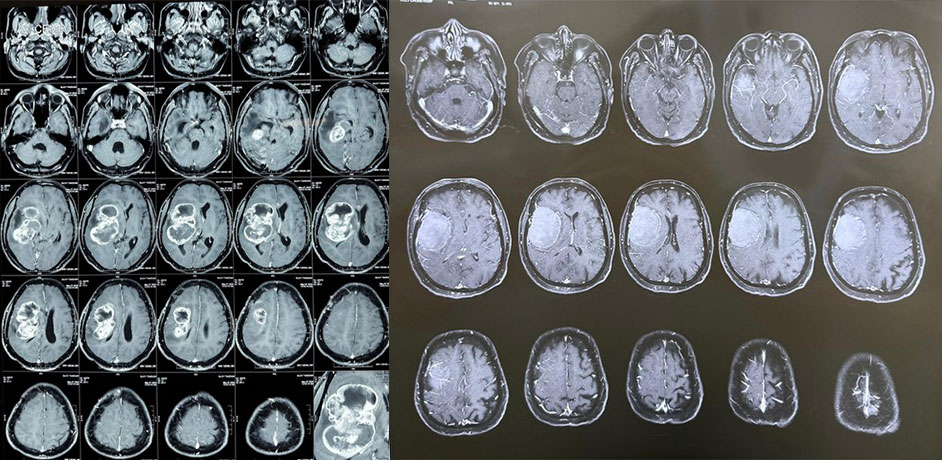

Dr. Ujwal Yeole specializes in navigation and ultrasound-guided tumor resections, offering advanced surgical precision for brain and spine tumors. These techniques allow real-time visualization of tumors, enabling safer removal while preserving surrounding healthy tissue.

With his extensive training and expertise, Dr. Yeole combines modern neuronavigation systems with intraoperative ultrasound to achieve maximum tumor removal while minimizing risks. This approach enhances surgical accuracy, improves outcomes, and shortens recovery time.